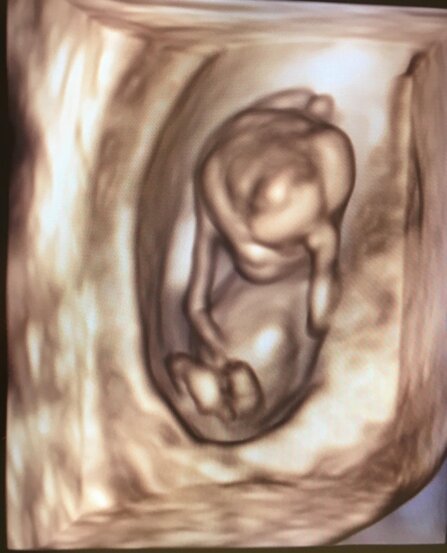

Ingresso 3, Piano 6, Ecografia e Diagnosi Prenatale: Sala Ecografica C.

PRESTAZIONI OSTETRICHE